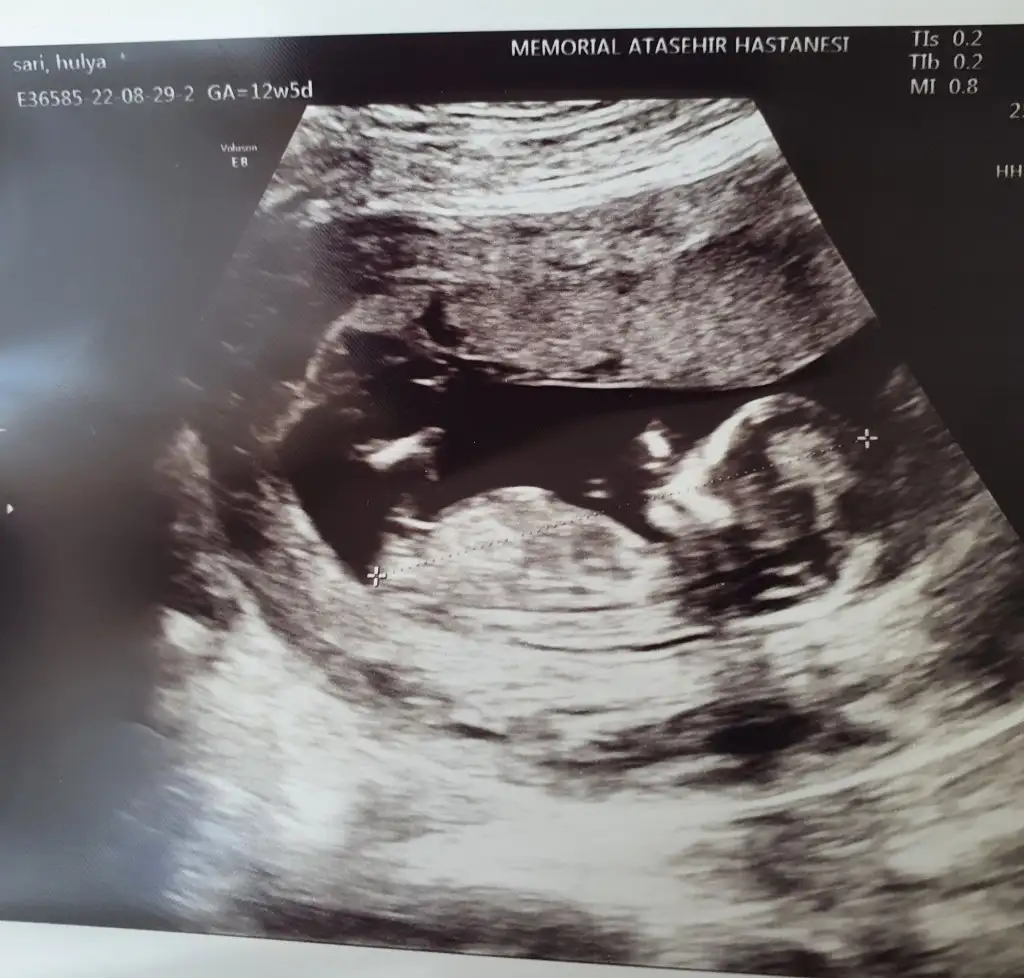

Güzel bir prenses diyorumBu da benim minnoşum:) cinsiyet hakkinda yorumları bekleriz, cok hareketliydi doktor bisey demedi

Erkek mi acabaBu da benim minnoşum:) cinsiyet hakkinda yorumları bekleriz, cok hareketliydi doktor bisey demedi

Erkek benceBu da benim minnoşum:) cinsiyet hakkinda yorumları bekleriz, cok hareketliydi doktor bisey demedi

Böyle fotograflardan pek anlamam hissetmem de ama sizjnkini görünce kız gibi geldi birkac kızı olan arkadaşlarımın ultrason görüntüsüne benzettimBu da benim minnoşum:) cinsiyet hakkinda yorumları bekleriz, cok hareketliydi doktor bisey demedi

Erkek gibi annesiBu da benim minnoşum:) cinsiyet hakkinda yorumları bekleriz, cok hareketliydi doktor bisey demedi

Erkek bence